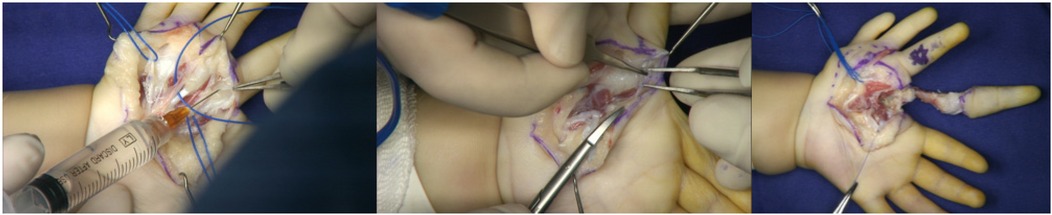

Abstract Congenital anomalies of the hand and forearm present a complex challenge in plastic and pediatric surgery. We present the case of a 13-month-old child with a congenital left mirror deformity, characterized by the presence of eight digits and two ulnae exhibiting near-perfect bilateral symmetry. A novel palmar-based incision design was employed for the corrective and functional reconstruction of the left hand,which may serve as a reference for the surgical management of similar conditions. Preoperatively, the radial-side middle finger demonstrated palmar opposition against the ulnar aspect of the palm.The surgical procedure included resection of the radial-sided index, ring, and little fingers , along with pollicization of the middle finger. Functional reconstruction of the neothumb involved restoring adduction and abduction using preserved native anatomical structures. Following comprehensive clinical and imaging evaluations, the patient underwent successful surgical treatment.Postoperatively, substantial improvements were observed in both hand morphology and grasping function. Through our novel palmar incision approach, we effectively reconstructed thumb opposition and adduction while preserving intrinsic hand musculature and achieving optimal scar concealment. In managing mirror hand deformities, meticulous selection of the most dominant digit for thumb reconstruction remains crucial. At the initial surgical stage, osteotomy of the selected digit was performed to enhance its morphological similarity to a normal thumb.